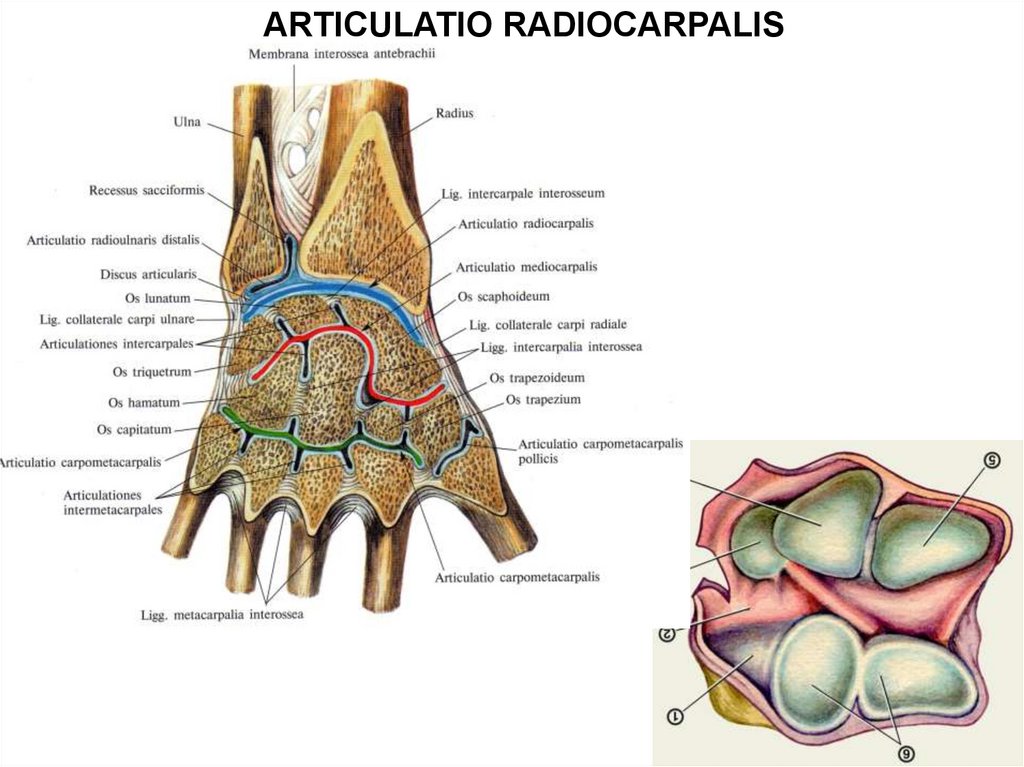

Анатомия кисти руки и строение костей